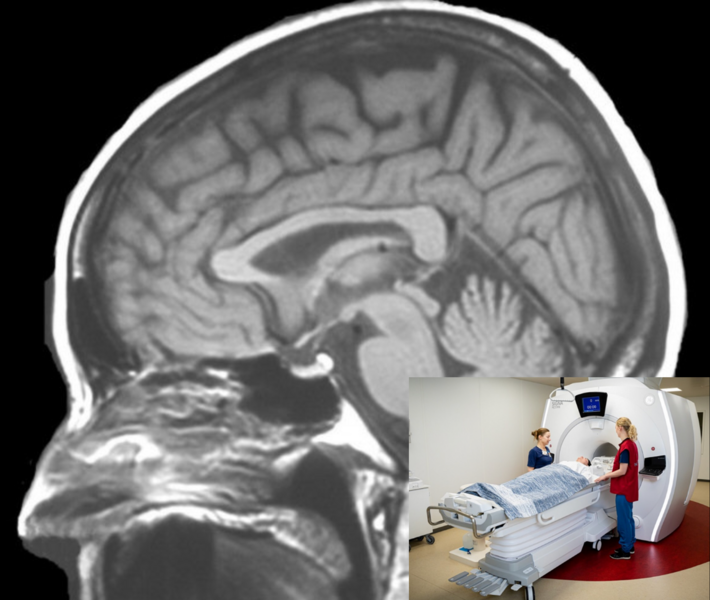

MRI scanning of the brain

During magnetic resonance imaging (MRI), multiple sequences are conducted including a T1-weighted anatomical sequence, a short-duration T2-FLAIR sequence to rule out other brain diseases, and a special neuromelanin sequence to measure the amount of neuromelanin in the brainstem. MRI is used to enhance the analysis of PET data and to measure certain brain systems that cannot be examined with PET scans.

During magnetic resonance imaging (MRI), multiple sequences are conducted including a T1-weighted anatomical sequence, a short-duration T2-FLAIR sequence to rule out other brain diseases, and a special neuromelanin sequence to measure the amount of neuromelanin in the brainstem. We also acquire a special diffusion tensor image (DTI) to study microstructural damage. MRI is used to enhance the analysis of PET data and to measure certain brain systems that cannot be examined with PET scans.